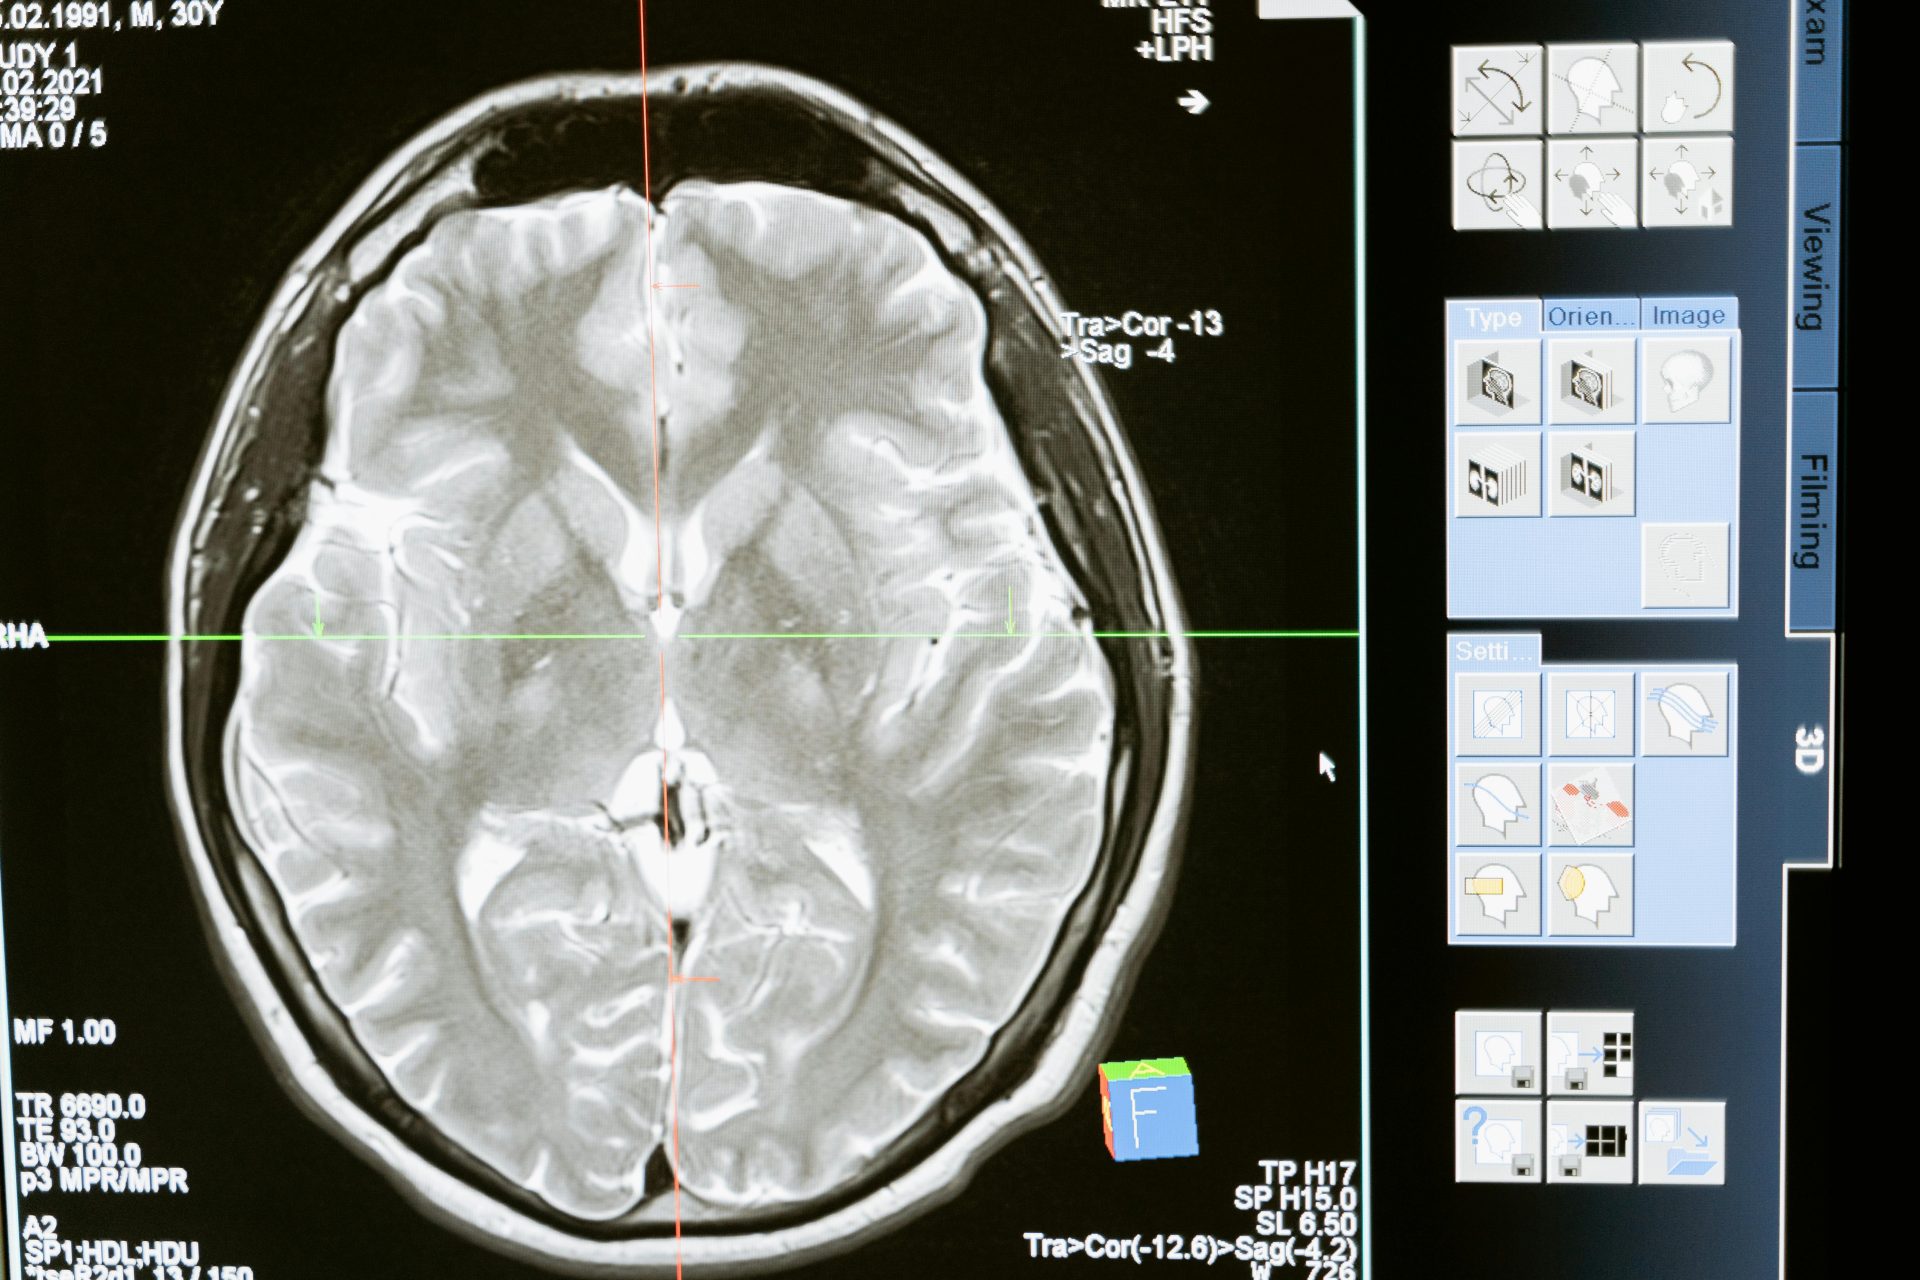

แม้เทคโนโลยีอัลตราซาวนด์จะถูกใช้มานานในงานถ่ายภาพทางการแพทย์ แต่ครั้งนี้เป้าหมายไม่ใช่การมองเห็นอวัยวะ หากเป็นการสื่อสารกับสมองโดยตรง แนวคิดนี้ถูกผลักดันโดย Gestala สตาร์ทอัพจีนอย่างที่ก่อตั้งในเมืองเฉิงตู ด้วยการพัฒนาอินเทอร์เฟซ BCI (Brain-Computer Interface) ที่ใช้ “คลื่นอัลตราซาวนด์แบบโฟกัส” เพื่อกระตุ้นและศึกษาการทำงานของวงจรประสาท

เมื่อเทียบกับอุปกรณ์ฝังในสมองที่ตรวจจับสัญญาณจากพื้นที่จำกัด ระบบอัลตราซาวนด์อาจเข้าถึงบริเวณสมองได้กว้างกว่า แต่การเปลี่ยนแนวคิดนี้ให้กลายเป็นข้อมูลที่แม่นยำและเชื่อถือได้ยังเป็นโจทย์ทางวิศวกรรมขนาดใหญ่

Gestala กำลังสำรวจว่าอัลตราซาวนด์สามารถใช้ตรวจจับรูปแบบกิจกรรมสมองที่สัมพันธ์กับอาการต่าง ๆ ได้หรือไม่ แนวคิดระยะยาวคือ ระบบสามารถวิเคราะห์สัญญาณที่เกี่ยวข้องกับความเจ็บปวดหรือภาวะซึมเศร้า แล้วส่งการกระตุ้นกลับไปยังจุดเฉพาะเพื่อปรับสมดุล